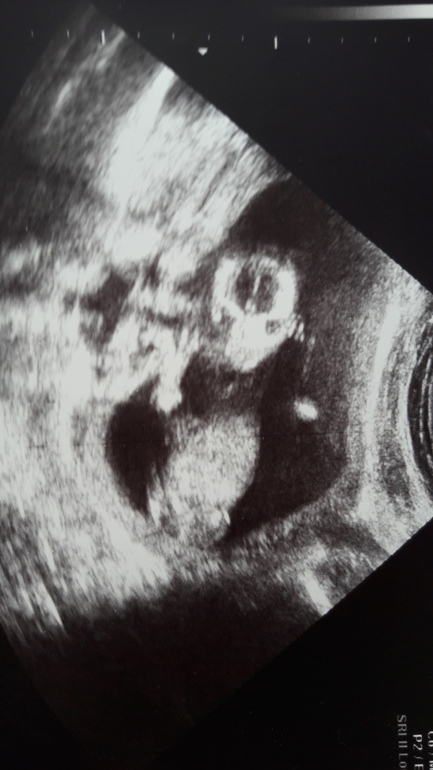

14н3д Узи! Фото ляли и пузззз!

Хорошее узи, малыш и мамин животик😘😘😘 нервы надо беречь. А у меня вообще нет живота😳 Моя сегодня по весу была 58 грамм

Наш первый скрининг и интрига месяца раскрыта😂😂😂❤️❤️❤️ Узи на 20 неделе. Низко лежит головка((